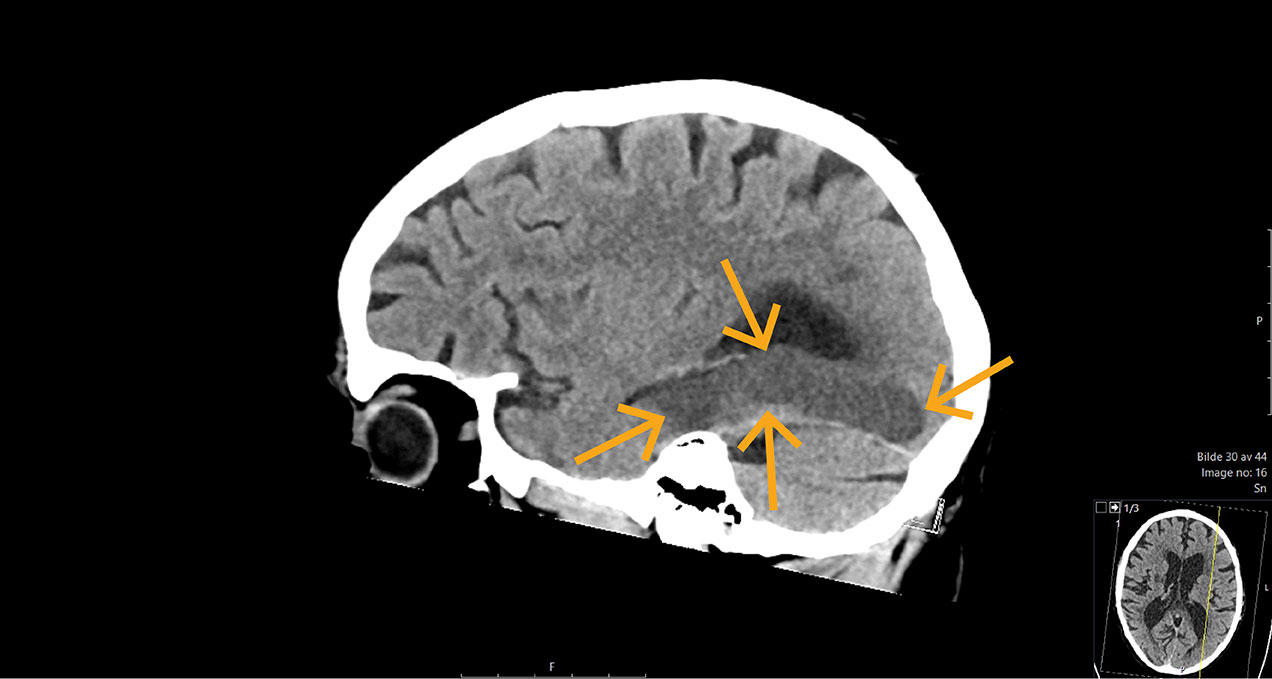

CT-bildet viser hypodensitet i forsyningsområdet til en gren (P2) av venstre arteria cerebri posterior hos en mann i 70-årene. Flere år tidligere hadde han et hjerneinfarkt i høyre hemisfære som ga ham en marginal spastisk hemiparese. Nå hadde han pådratt seg et nytt infarkt oksipito-temporalt som ga ham synsfeltutfall opp mot høyre (øvre høyre kvadrantanopsi). Filmen viser at han har vanskelig for å benevne gjenstander (nominal afasi) når de sees som symboler eller tegninger. Han har altså ikke visuell objektagnosi. Evnen til å lese var borte, men ikke evnen til å skrive. Fenomenet kalles aleksi uten agrafi. Dets forklaring ble først beskrevet i 1892 (1).

Fra oksipitallappen formidles prosessert synsinformasjon gjennom to atskilte informasjonskanaler. Den ene går til parietallappen for lokalisering av objekter, og for samspill med motoriske områder for målrettet bevegelse, f.eks. å skrive. Den andre går til temporallappen for gjenkjenning av hva en ser, og for samspill med Wernickes språkområde for benevning og forståelse. Et eget område i nedre mediale del av temporallappen, bakre del av gyrus fusiformis, er dedikert til gjenkjenning av bokstaver og ord (2), det såkalte visuelt ordgjenkjennende området. Som oftest er dette området lokalisert på venstre side, samme side som Brocas og Wernickes språkområder.

Tradisjonelt oppstår ren aleksi ved skade i venstre oksipitallapp, som også omfatter bakre del av hjernebjelken (splenium corpus callosum). Denne delen inneholder fibrene som overfører informasjon fra høyre synsfelt til det ordgjenkjennende området og Wernickes område. Hos vår pasient var hjernebjelken intakt, og det var sannsynligvis omfattende skade i det ordgjenkjennende området som forårsaket pasientens «ordblindhet». Fordi pasienten hadde pacemaker, ble det ikke tatt MR-bilder. Hans tidligere infarkt i høyre hjernehalvdel hadde neppe betydning for det observerte fenomenet.